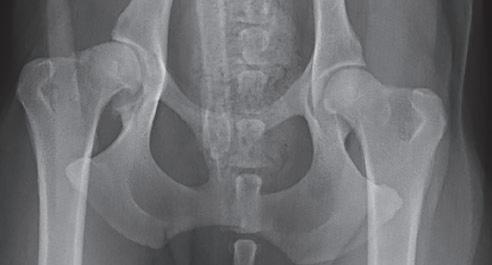

Displasia de cadera (I): etiopatogenia, signos clínicos y pruebas diagnósticas 26